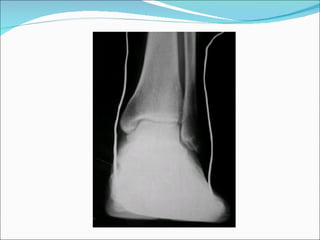

Cliché de cheville de profil externe: Position  :  décubitus latéral sur le côté à examiner.  Du côté sain la cuisse est fléchie sur le tronc et la jambe est fléchie sur la cuisse, le genou repose sur un coussin de façon à garder une position stable.  La jambe du côté à examiner est en rotation interne, de façon à ce que la ligne bi-malléolaire soit perpendiculaire au plan horizontal. Il faut ainsi écarter la pointe du pied du plan de la table avec un sac de farine d'épaisseur suffisante. Cette manoeuvre n'est pas toujours répétitive dans le temps.

Cliché de cheville de profil externe: Centrage  : un centimètre au-dessous de la malléole interne Rayon directeur vertical .

Résultats extrémité inférieure du tibia et du péroné l'articulation tibio-tarsienne de profil articulation sous-astragalienne de profil, le talon et les parties molles talonnières, l'articulation de Lisfranc, le scaphoïde et le cuboïde.

Le  critère de réussite   Astragale vu sous une courbe semi-circulaire unique, et non dédoublée. En arrière on observe la partie postérieure du talon, le calcanéum, le tendon d'Achille.  En avant du tendon d'Achille une zone claire triangulaire entre les muscles postérieurs de la jambe, le tendon d'Achille et le bord supérieur du calcanéum intitulé triangle de Kager